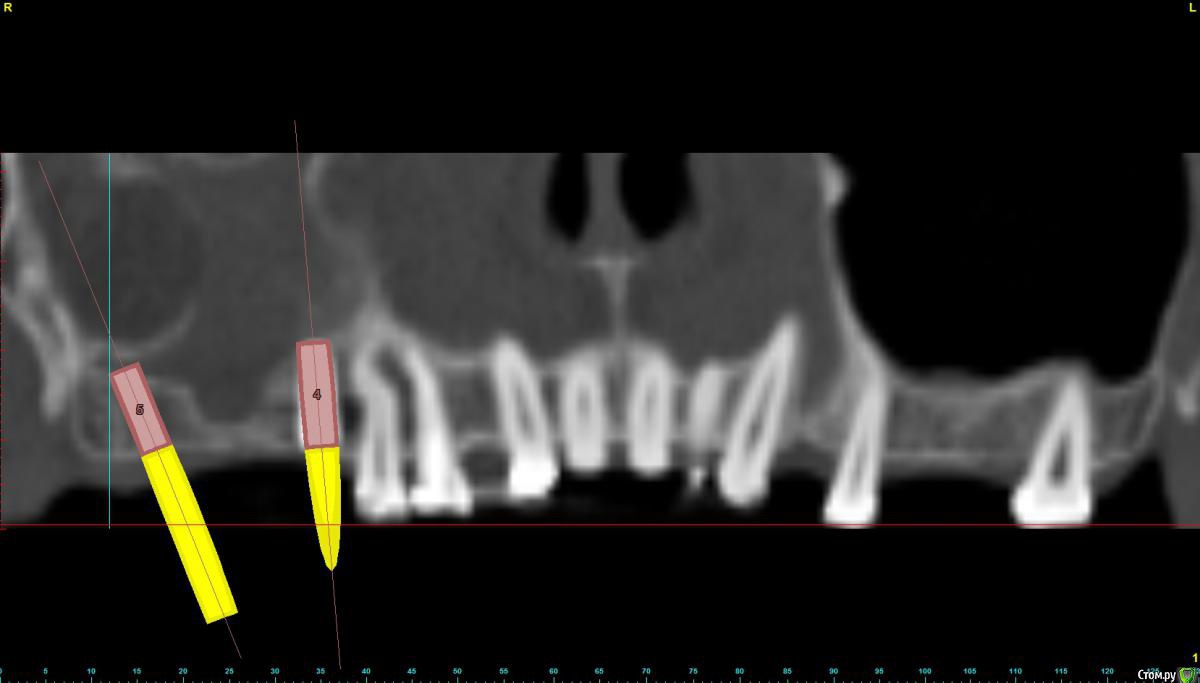

bullbull Опубликовано 8 апреля, 2015 Поделиться Опубликовано 8 апреля, 2015 Здравствуйте.Обратилась пациентка со следующей ситуацией.Имплант 16 уже стоит (альфа-био). В области 17 кость 2-2,5 мм. Пазуха тотально затемнена, ЛОР патологию отрицает. Возможна ли постановка имплантата под углом на уровень 18 зуба? Размер имплантата 4,10 Ссылка на комментарий

johniola Опубликовано 8 апреля, 2015 Поделиться Опубликовано 8 апреля, 2015 я ставил таким образом,только угол чуть больше.да и ставьте 13 мм Ссылка на комментарий

bullbull Опубликовано 9 апреля, 2015 Автор Поделиться Опубликовано 9 апреля, 2015 (изменено) Нет. Это не киста, просто панорамная кривая так выставлена.Здесь имеет место анатомическая особенность. На аксиальном срезе на уровне верхушек клыков видно, что отсутствует передняя стенка гайморовой пазухи и мягкая ткань заполняет весь просвет. Кроме того пациентка уверена, что зубы в 1-м секторе помогут решить проблему асимметрии лица. Изменено 9 апреля, 2015 пользователем bullbull Ссылка на комментарий